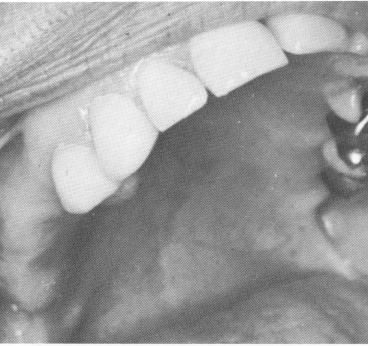

Fig. 11-42. The two anterior teeth prepared for full crown restorations.

2 Maxillary anterior teeth prepared for full crown restoration